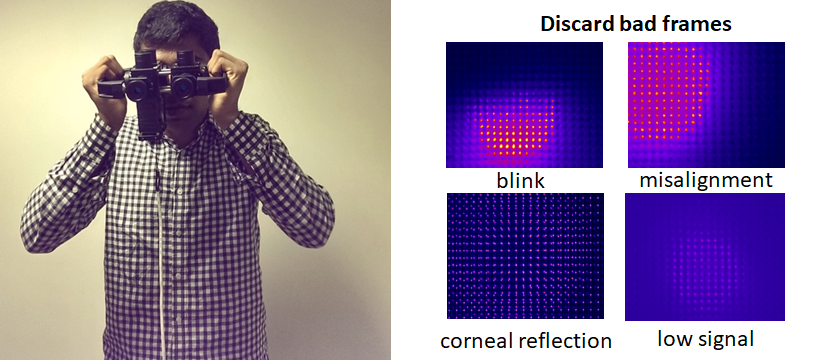

PurposeModern autorefractors have demonstrated high accuracy and higher repeatability than manifest refraction in adults yet are not considered precise enough to substitute the gold standard, even in low-resource settings where there is a severe shortage of experienced refractionists. This work evaluates a novel approach that combines dynamic wavefront aberrometry data, acquired using an affordable portable autorefractor, with the analysis of retinal image quality metrics (IQMs) to predict subjective refraction. Methods56 subjects (34±14 years) were recruited for the analysis. Each participant underwent standard clinical refraction followed by a 10-second video acquisition using a QuickSee (QS) wavefront aberrometer (PlenOptika, USA). Shack-Hartmann images of each video for the right eye were processed to obtain Zernike coefficients up to the 4th order. Coefficients obtained for each image were mathematically corrected with the closest sphero-cylindrical correction and the residual wavefront error was used to calculate the Point Spread Function (PSF) and IQMs (e.g., Strehl Ratio) describing some performance parameter of the corrected eye. Since each IQM is part of a dynamic sequence, it is possible to build a dynamic signal for each metric which contains information about fluctuations in image quality during the measurement. The final refraction is obtained as the average of the refractions corresponding to the images whose IMQs provided optimal performance. ResultsThe proposed method reduced the differences between QS and manifest refraction. Specifically, for spherical equivalent refraction (M) (Table 1) a 79% average reduction in MBE together with moderate average improvements for MAE (10.3%), LOA (5%), and percentage of agreement within 0.25D (8.8%) and 0.5D (6.3%) were found for all IQMs evaluated. ConclusionsThe proposed algorithm behaves as an efficient filter which selects those measurements within the dynamic sequence that are more representative of the manifest refraction of the patient. |